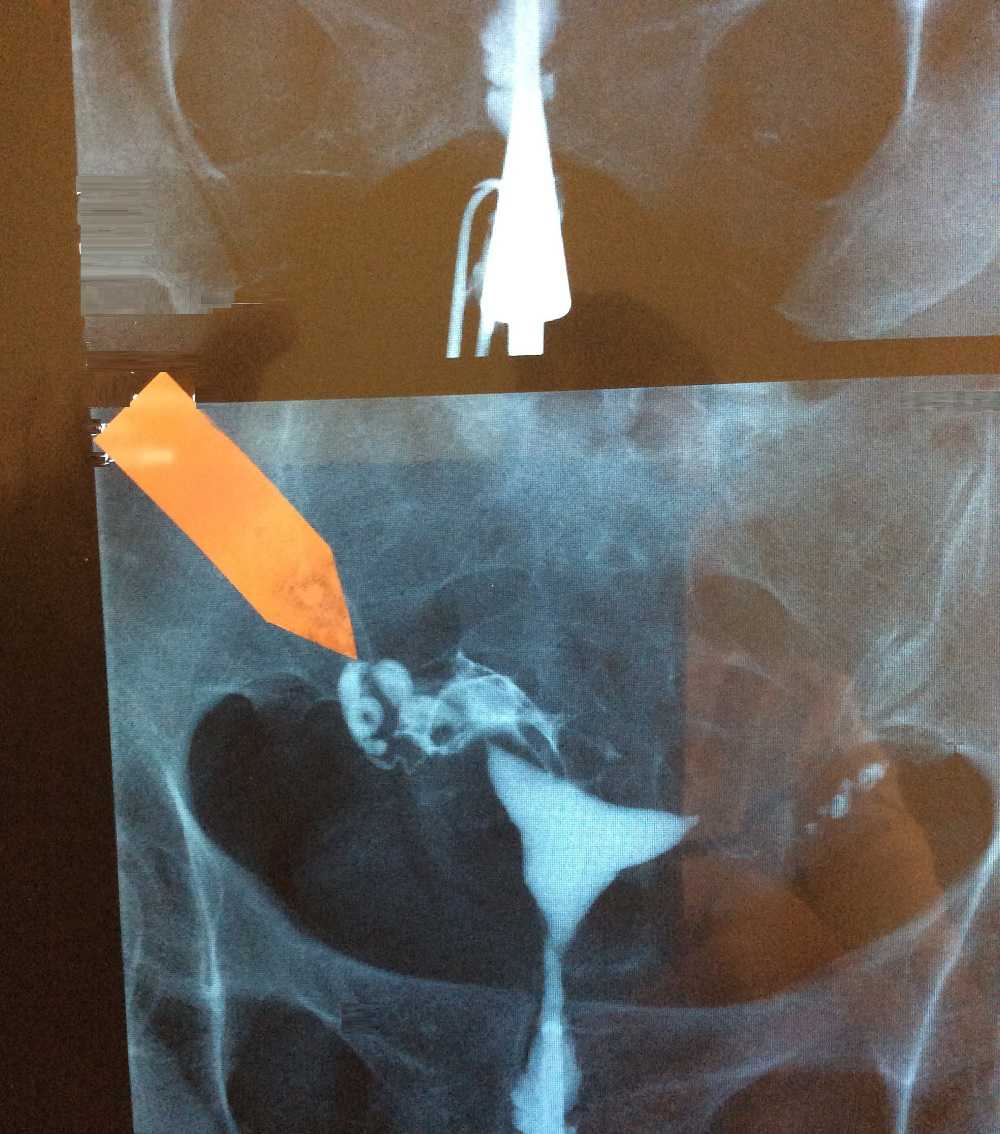

Гистеросальпингография: описание и фотографии